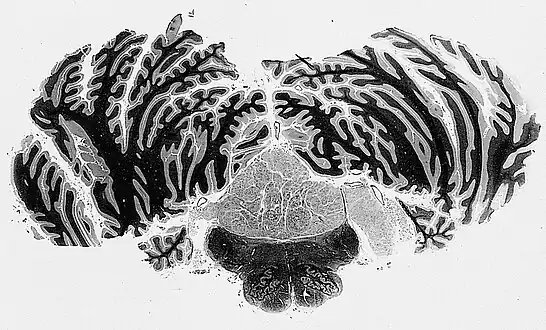

Subependymomas of the fourth ventricle, extending into the cerebellopontine angle via the foramen of Luschka, right side of illustration.

On a CT, it often shows a less dense to equally dense mass. If it is big, it may have parts that are cystic or calcific.[2] In 50-60% of cases, the tumor is in the fourth ventricle, while the second most common (30-40% of cases) location is the side ventricles. It is rare for it to be in the third ventricle or the central canal of the spinal cord.[2]